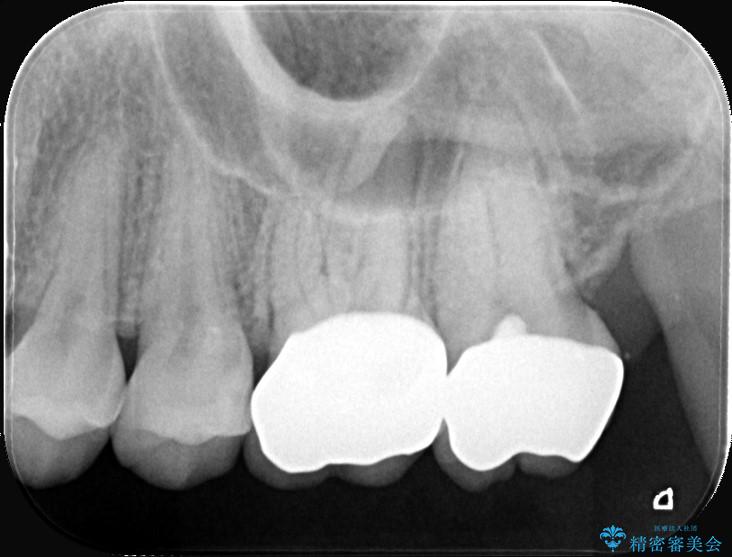

精密検査の結果、非常に深い虫歯があり、通常であれば抜髄が必要な状態でした。

しかし、神経を抜くと歯の寿命が縮まってしまうため、今回は神経の一部を温存する部分的断髄法(VPT)を提案しました。

高い殺菌性と封鎖性、そして組織の再生を促す効果を持つMTAセメントを使用して神経を保護し、最終的には強度と審美性に優れたセラミックで修復する計画を立案しました。

部分的断髄法(MTAの使用): ラバーダム防湿を行い、無菌的な環境下で虫歯を慎重に除去。神経の露出を確認した後、炎症を起こしている一部の神経のみを除去し、残りの健全な神経を保護するためにMTAセメントを充填しました。これにより、神経の機能を維持し、歯を内部から守ることが可能となりました。